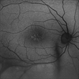

- maculoschisis, foveoschisis

- HD 6x6 OCT-Angiography Structural View of the Deep Inner Retina